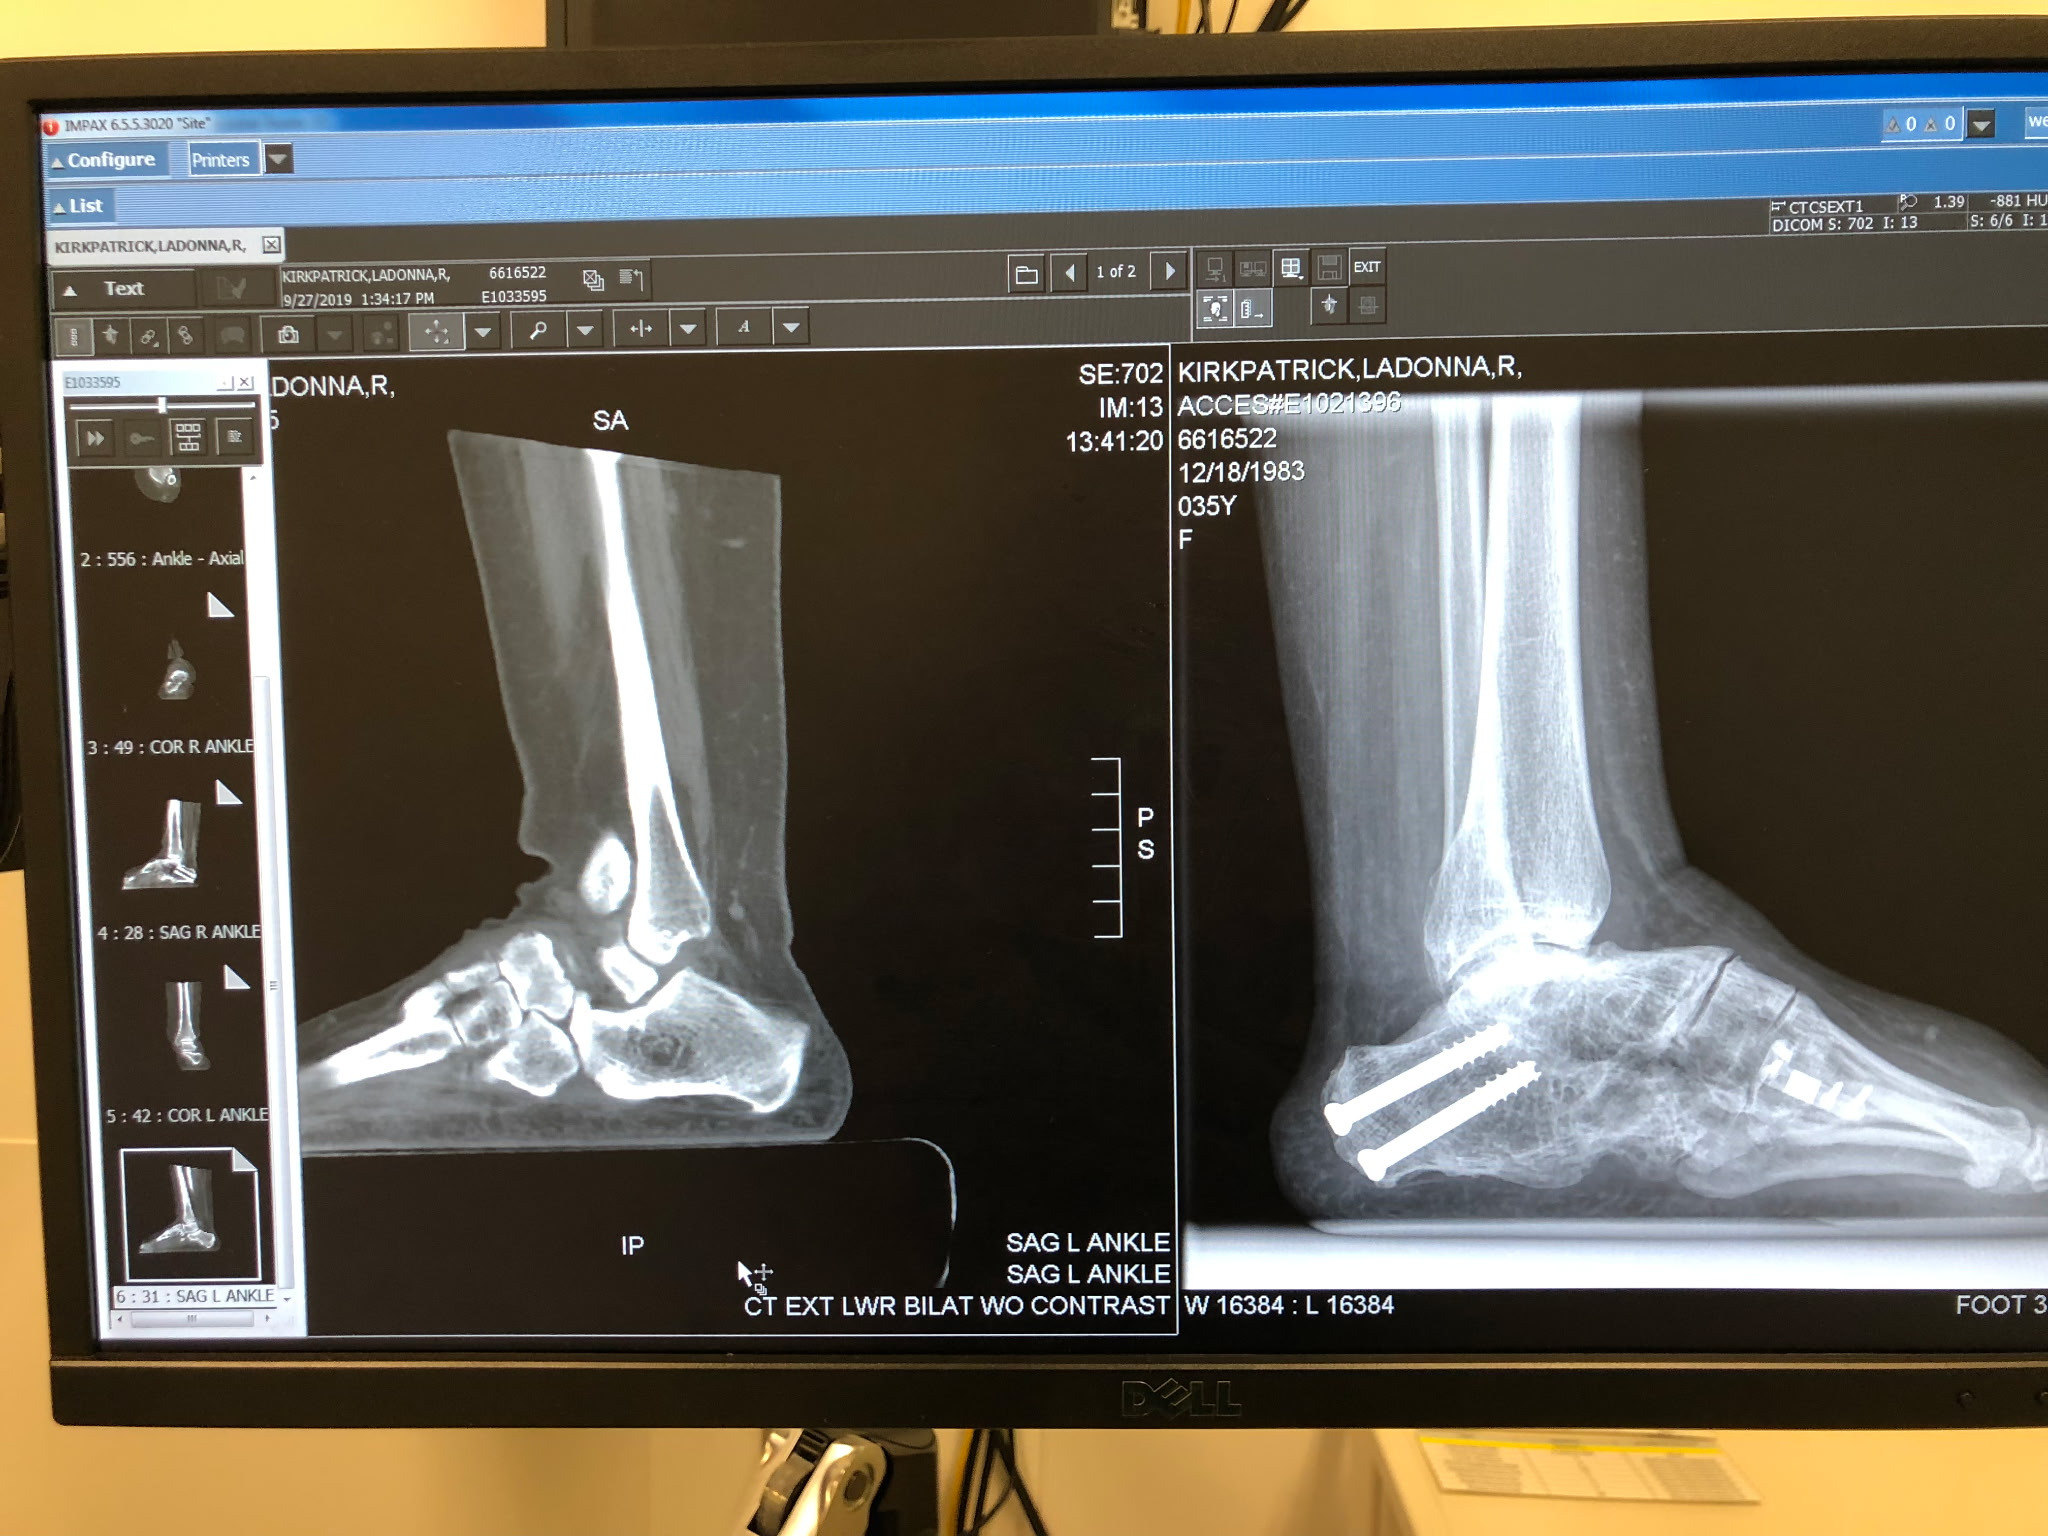

One week ago, LaDonna Kirkpatrick received heartbreaking news from her doctor: Without a specialized prosthetic device known as the ExoSym for both of her legs, she may never walk again and will face the strong possibility of amputation.

LaDonna was born with Bilateral Clubfeet, a condition that affects over 200,000 children around the world each year. Growing up in foster care, she spent her childhood fighting for proper medical care—undergoing multiple painful surgeries and recoveries in hope of one day walking, running, and living the active life she dreamed of and worked so hard for.

Her Orthopedic Surgeon, Dr. Meeker, recommends the ExoSym prosthetics to avoid dangerous surgery that could leave her permanently in a wheelchair without the ability to walk.. LaDonna’s hope is simple, relatable, and powerful: to walk hand-in-hand with her husband, to play with her kids, and to reclaim the freedom so many of us take for granted.